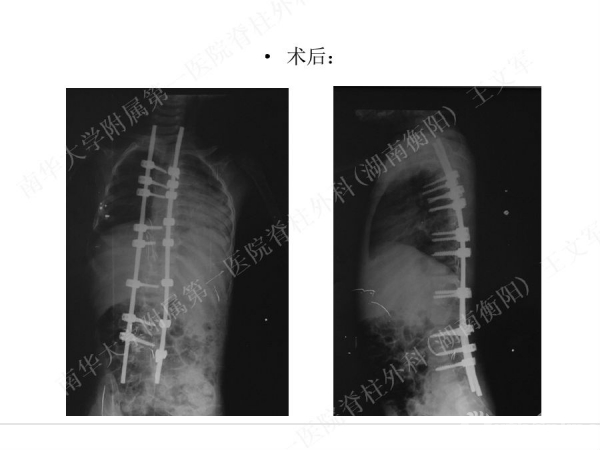

拥有完全自主知识产权的滑槽钉生长棒非融合技术,由南华大学附属第一医院脊柱外科王文军教授研发。

该技术在提供良好矫形固定效果的同时,保留了脊柱生长潜能、尽可能减少对患儿脊柱生长的影响,初步临床效果显示该系统是简单安全有效的,是严重儿童早发脊柱侧弯矫形治疗的一种有益尝试。

擅长脊柱脊髓疾病的微创及非融合手术治疗,目前率领科室开展的先进微创手术有:椎间孔镜技术、经皮穿刺腰椎外固定支架术治疗胸腰椎骨折、腹腔镜下人工腰椎间盘置换术、胸腔镜下胸椎前路手术、腰骶椎轴向融合术。率先在全国业界提出组合微创技术的理念,大大提升了脊柱微创技术的应用范围和治疗效果。拥有自主知识产权的生长棒技术在早发性脊柱侧弯术中的应用解决了儿童脊柱侧弯既早期矫形,又不影响生长发育的世界性难题。